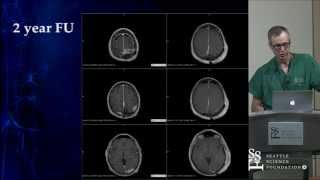

Treatment of Dural Arteriovenous Fistulas by Cameron McDougall, M.D.

Treatment of Dural Arteriovenous Fistulas was presented by Cameron McDougall, M.D. at the Seattle Science Foundation for the 1st Annual Cerebrovascular ...

Seattle Science Foundation